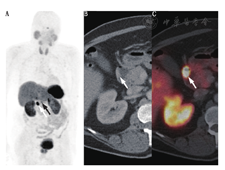

结合PET/CT的自身优势(更高的空间分辨率和灵敏度)并通过改良药理特性,将能检测较小病变或中度SSTR表达的病变,提高诊断的灵敏度和准确性(图1和图2)。

68Ga-肽PET显像在非胰腺和胰腺NETs有类似的作用(图1,图2,图3)。68Ga-肽PET显像对1型多发性内分泌腺瘤也很灵敏。在19例1型多发性内分泌腺瘤患者中进行68Ga-DOTATOC与111In-喷曲肽及增强CT的对比研究,结果显示68Ga-DOTATATE检出NETs的灵敏度为76%,111In-喷曲肽为20%,增强CT为60%;68Ga-DOTATOC检出胰腺肿瘤46个,111In-喷曲肽检出11个,增强CT检出37个[29]。一项前瞻性研究包括26例1型多发性内分泌腺瘤,对患者行68Ga-DOTATATE、111In-喷曲肽和增强CT,结果显示68Ga-DOTATATE PET/CT显像检出107个病灶,111In-喷曲肽SPECT/CT检出33个病灶,增强CT检出48个病灶;26例患者中8例(31%)因68Ga-DOTATATE PET/CT的结果而改变治疗计划,而111In-喷曲肽SPECT/CT或CT无阳性发现[30]。